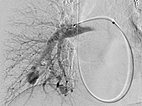

Upon evaluation of the underlying disease, contrast ultrasonography revealed a pulmonary right-to-left shunt, and computed tomography confirmed the finding of multiple pulmonary AVMs. Because of the size, there was an indication for embolization. Digital subtraction angiography demonstrates a pulmonary AVM in the upper lobe, already superselectively catheterized, with typical aneurysmally dilated arteriovenous shunt.

Occlusion of the pulmonary AVM of the upper lobe by insertion of multiple platinum wire loops (coils) via a microcatheter while sparing non-pathological pulmonary arteries.